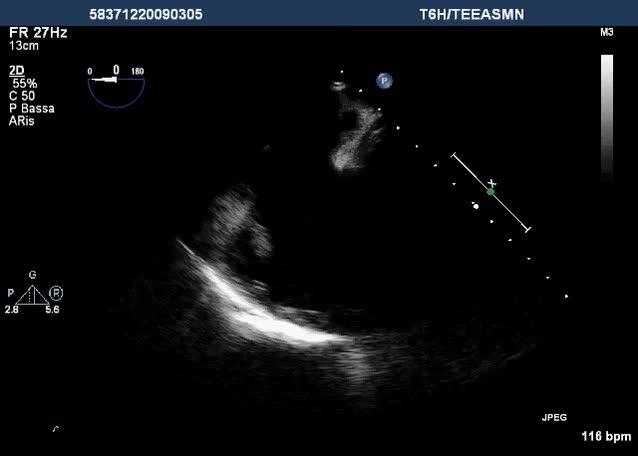

Aorta quadricuspide

Laura Toffetti